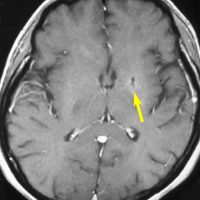

若い患者さんのリンパ腫です。左が診断時MRIで,黄色の矢印でみれる3ヶ所に同時にリンパ腫が発生しています。定位生検術後にすぐにMTX化学療法を3コースしたら,真ん中の画像になりました。ほとんど消失しているのですが,矢印の先にぼーっと少し残っているのでCR(消失)とはいいません。化学療法を終えた後に全脳照射30グレイをしたら右の画像になり治りました。これは順調な治療経過の例です。